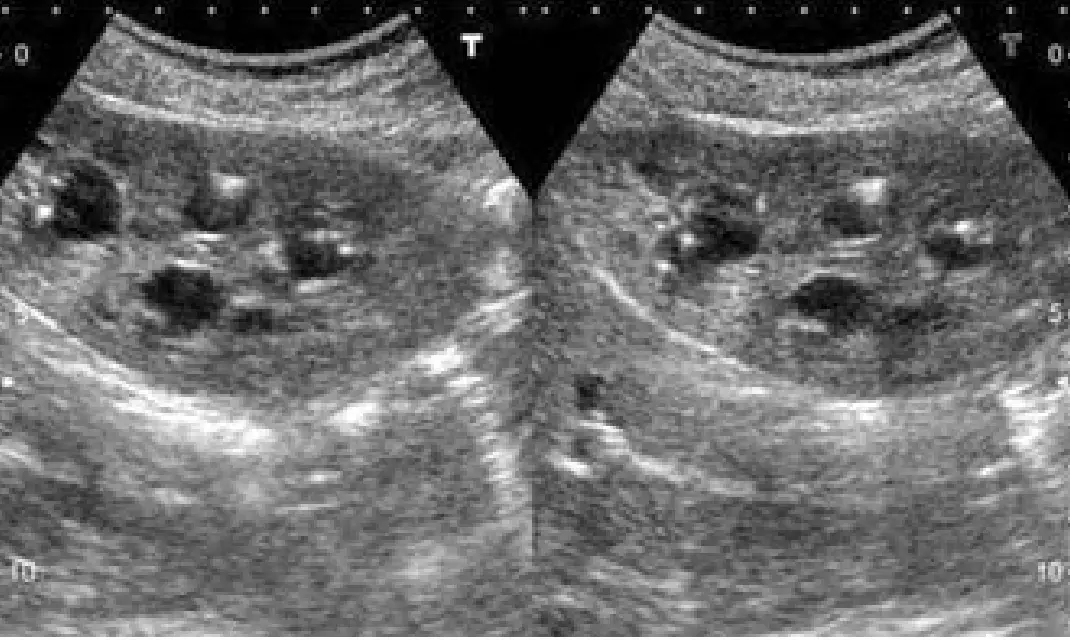

本題為腎臟超音波影像判讀與慢性腎病鑑別診斷題。63 歲女性,有高血壓與退化性關節炎史(使用止痛藥),出現蛋白尿(2+)、血尿(5-10 RBC/HPF)、血肌酸酐 2.2 mg/dL、輕度貧血,超音波顯示雙側腎臟均輕度萎縮(各約 9 公分)。考核的是依據「雙側腎臟萎縮」這一重要影像特徵,排除哪些診斷「不可能」成立。題目問的是**「不可能之診斷」**——即以影像與臨床特徵無法解釋者。

超音波圖片顯示左右腎臟各一個切面,為標準腎臟縱切面超音波影像(灰階 B 型超音波)。主要所見:

- 雙側腎臟萎縮:兩側腎臟測量均約 9 公分(成人正常為 10–12 公分),輕度縮小。

- 腎臟內多發性低回音結構:可見多個大小不等的圓形或橢圓形無回音至低回音區,分布於腎實質中,形態符合多發性腎臟囊腫(multiple renal cysts)。

- 整體腎實質回音:皮質與髓質回音偏強,皮髓質分界尚存,但腎臟整體輪廓略為縮小。

臨床意義:雙側腎萎縮合併多發性囊腫,提示這是一個長期、慢性的腎臟損傷過程(chronic kidney disease, CKD),而非急性/進展中腎臟損傷。特別是:腎臟萎縮代表慢性不可逆的纖維化,萎縮 + 囊腫的組合對鑑別診斷具有重要限縮作用。